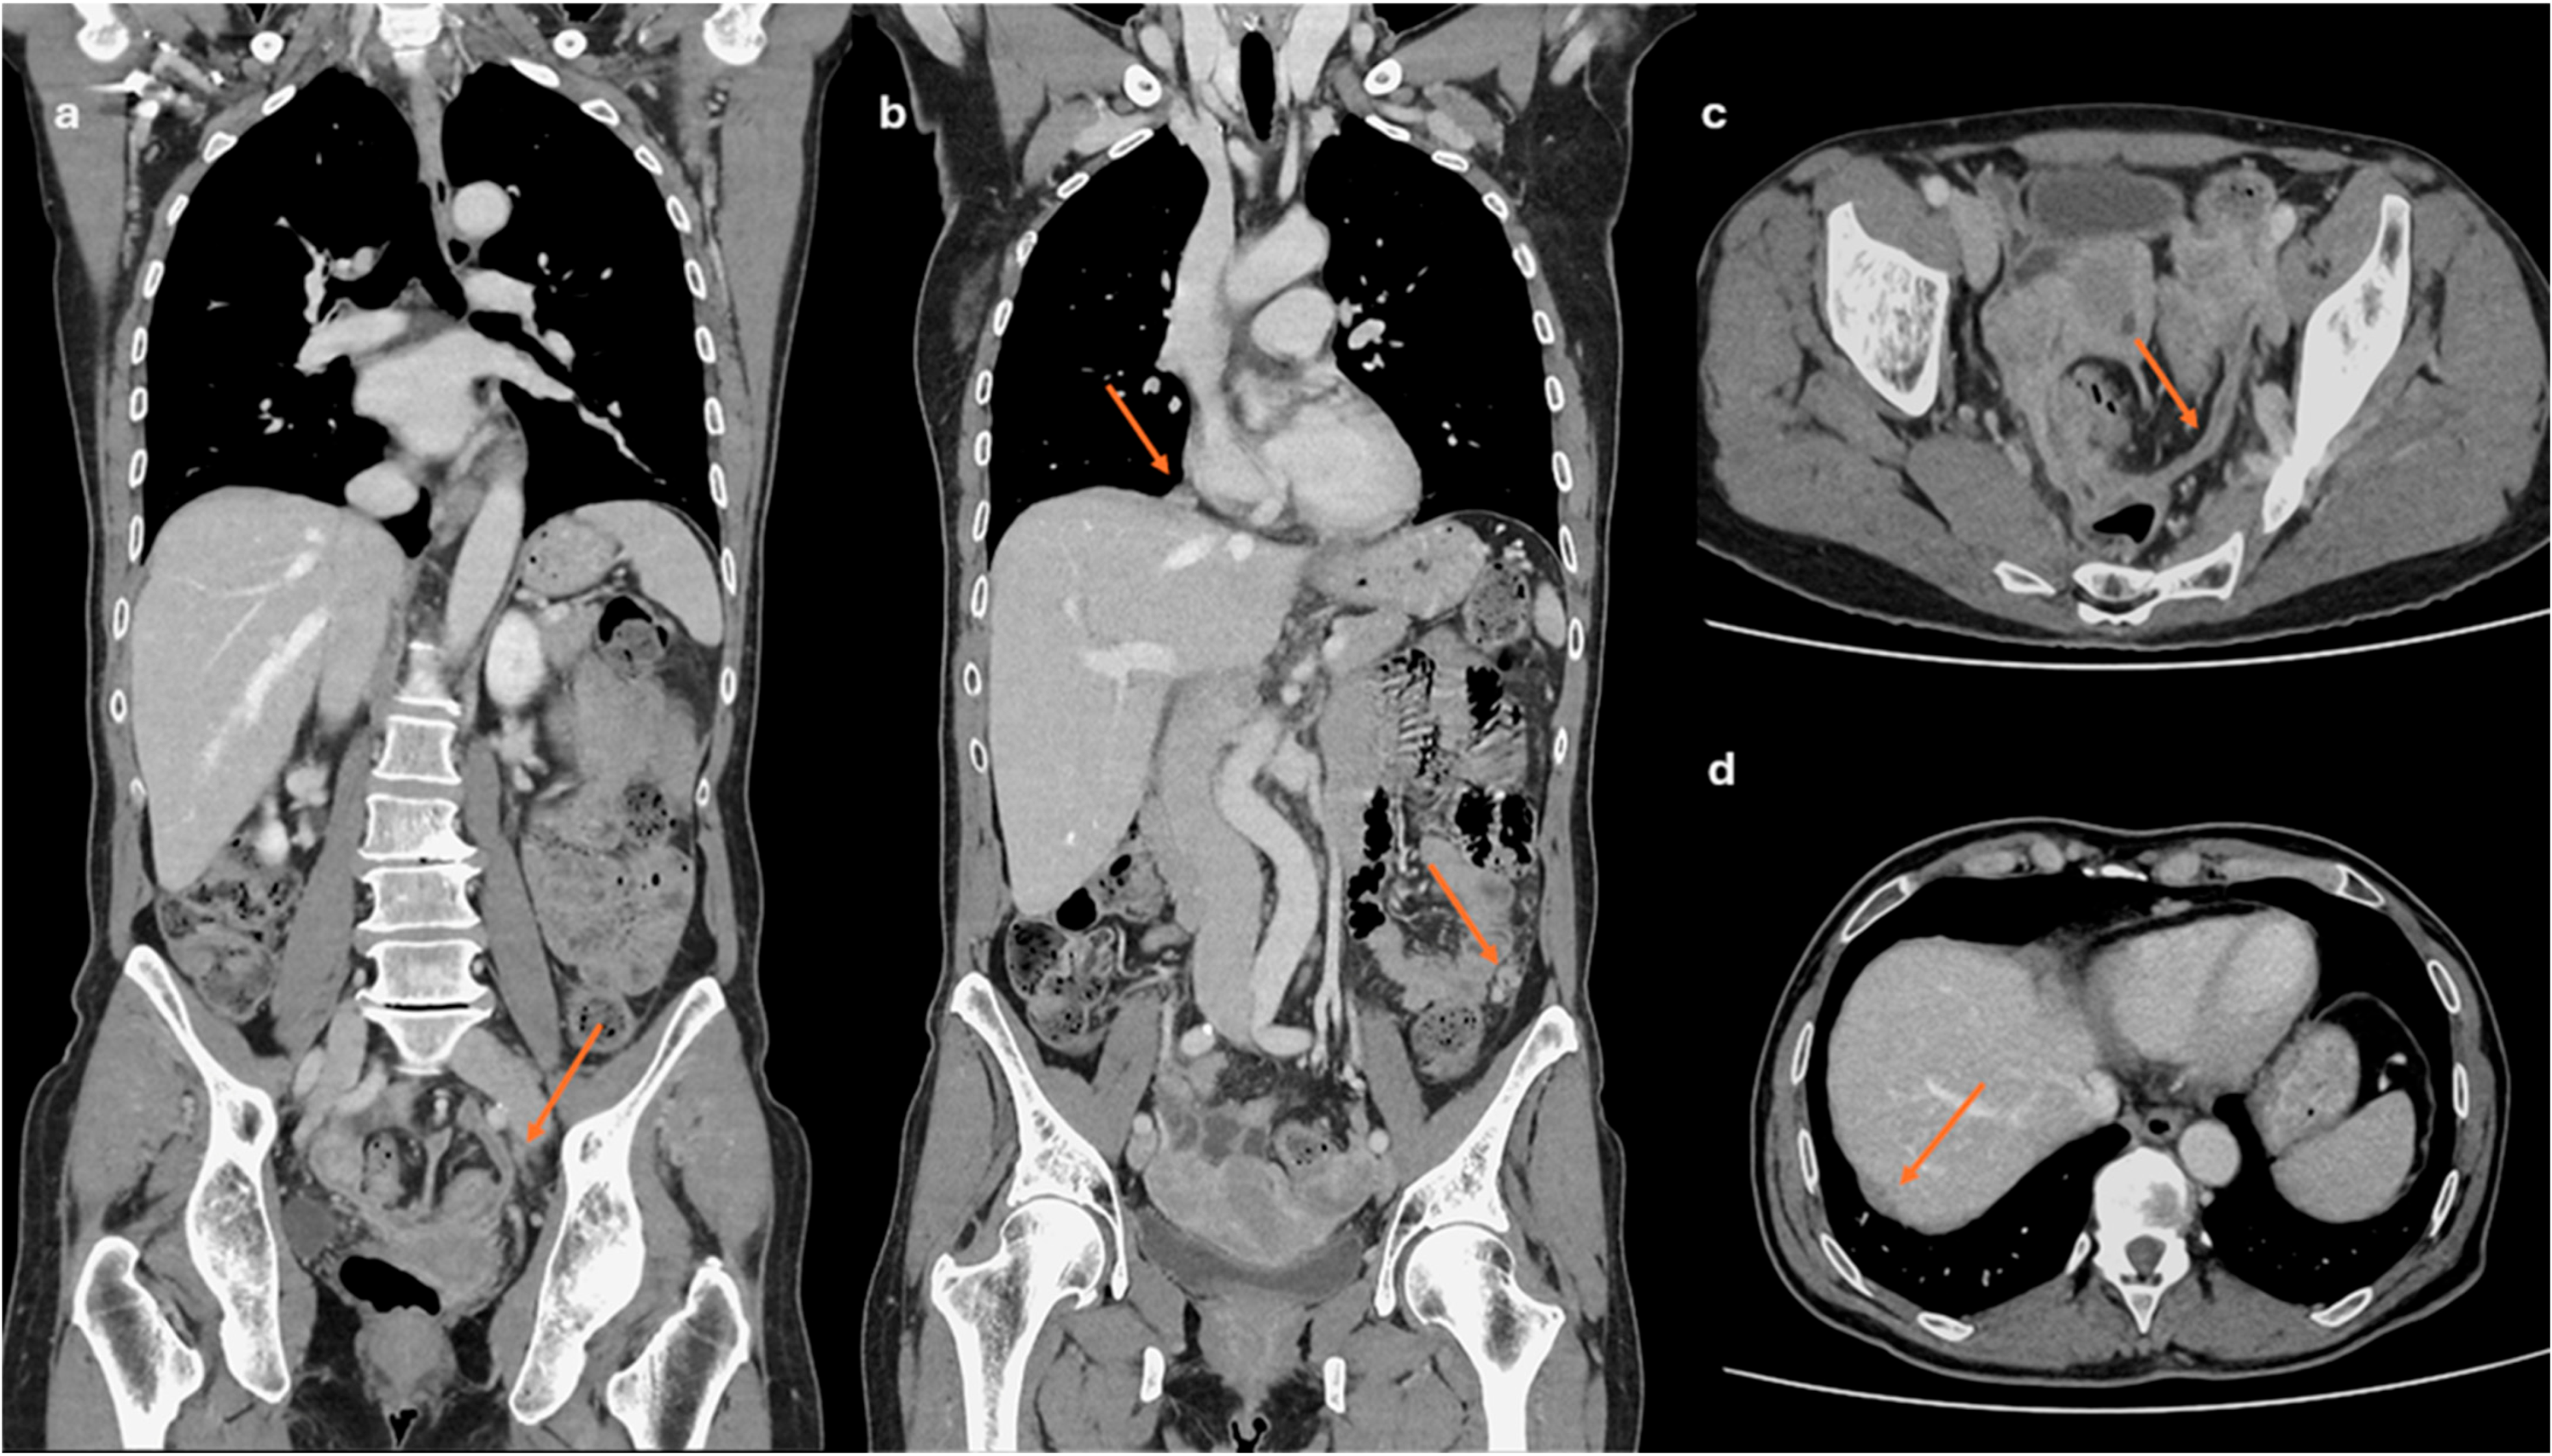

2.2. CT Imaging

- Lesions associated with the presence of peritoneal implants and/or secondary disease localization (Figure 6)

- Prediction of disease spread at diagnosis: AI can automate the process of image segmentation, i.e., the isolation and analysis of suspicious areas in medical images. This segmentation allows radiologists to focus more accurately and quickly on potentially pathological areas. Indeed, although CE-CT is the gold standard for staging ovarian cancer, it has accuracy limitations in identifying small peritoneal implants (<1 cm) and localizations in specific areas such as the small bowel and mesentery. In addition, lesions are often “unmeasurable” according to RECIST 1.1 criteria [68]. Several studies describe how AI can predict the presence of peritoneal carcinosis and lymph node metastasis in HGSOCs on both CT and MR imaging by integrating radiomics with both clinical and laboratory factors such as age and CA-125 blood-levels [69,70,71].

- Avesani, G.; Arshad, M.; Lu, H.; Fotopoulou, C.; Cannone, F.; Melotti, R.; Aboagye, E.; Rockall, A. Radiological assessment of Peritoneal Cancer Index on preoperative CT in ovarian cancer is related to surgical outcome and survival. Radiol. Med. 2020, 125, 770–776. [Google Scholar] [CrossRef] [PubMed]